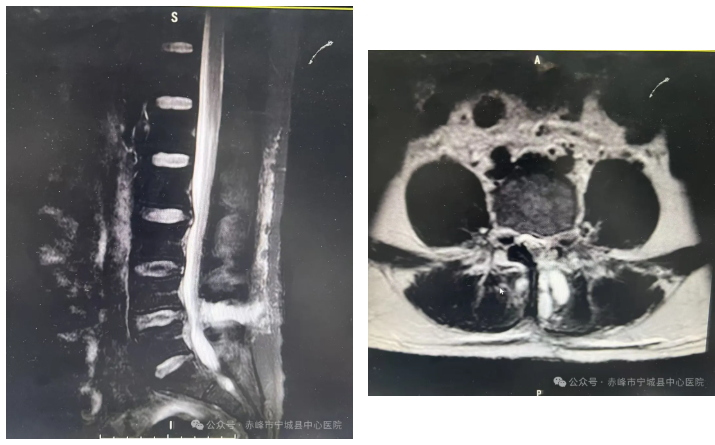

一:腰椎间盘突出症

术前影像